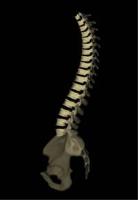

また、擬似的に三次元画像を作成することで、立体的に椎体の配列を観察することも可能です。